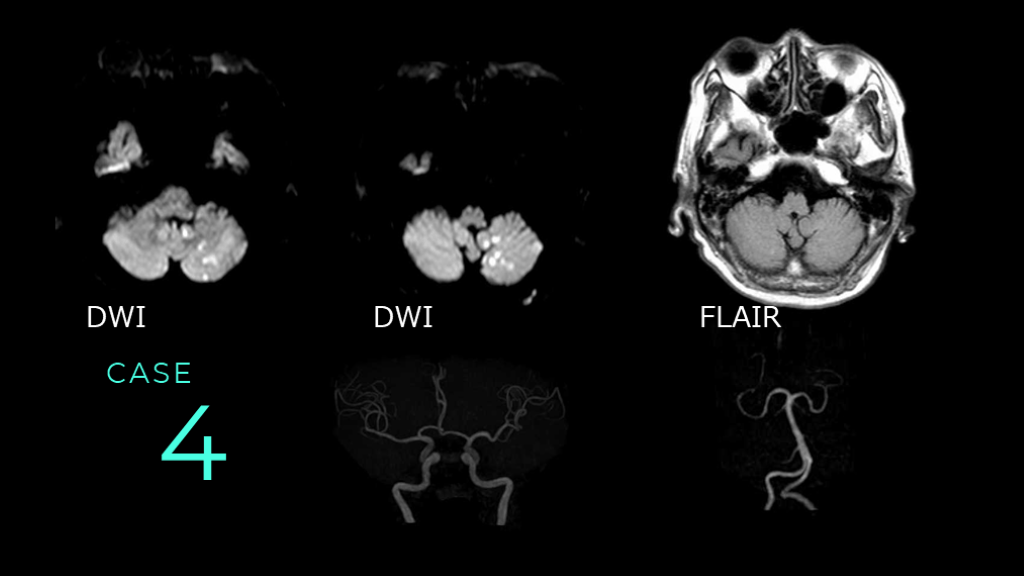

CASE 4 DWI DWI FLAIR

CASE 4 DWIでは、左側小脳に散在性の高信号病変を認める。 同病変はFLAIRでは目立たない。 DWI DWI FLAIR

#54.

CASE 4 MRAでは粗大な血管狭窄病変は、前方循環と後方循環ともに、目立たない。後方循環系は血管蛇行が認められる。

#55.

CASE 4 コメント:小脳梗塞症例。小脳への血流は後方循環系によるので、臨床情報としては、後方循環系の血管狭窄があるかどうかが知りたい内容になります。